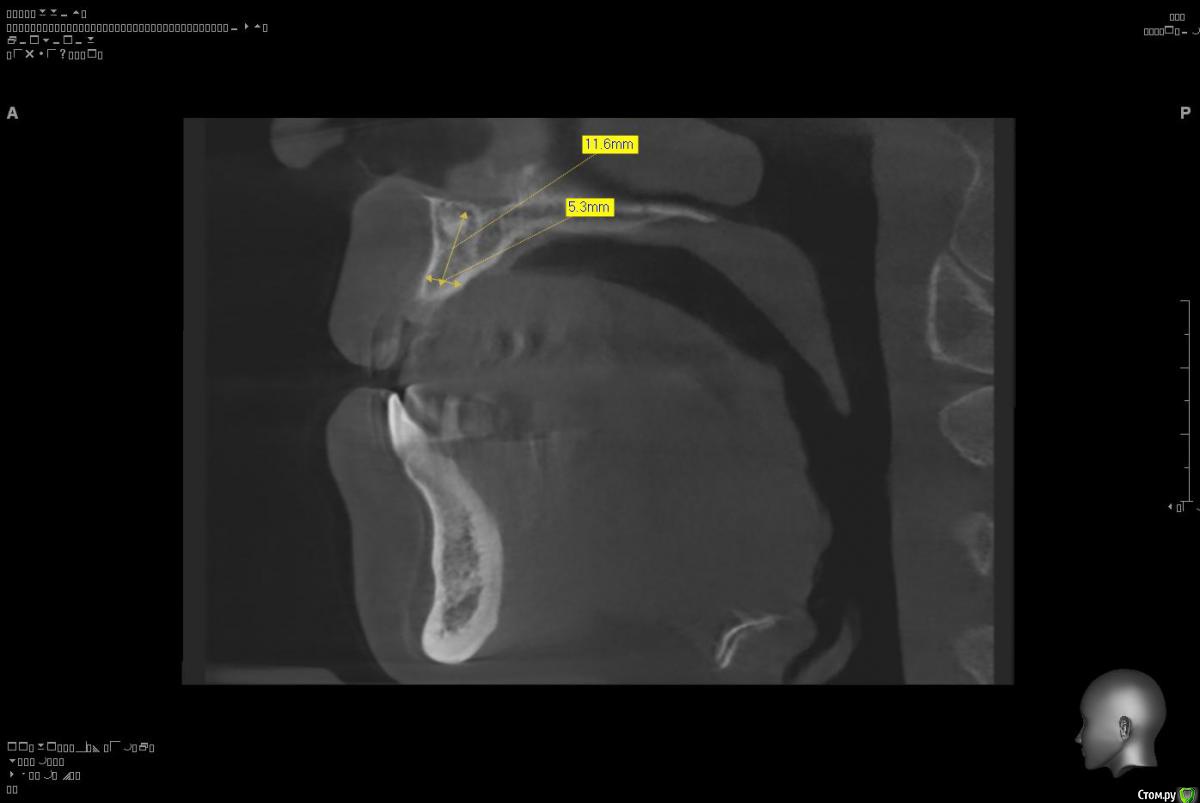

Platon Опубликовано 10 января, 2016 Поделиться Опубликовано 10 января, 2016 Здравствуйте.Помогите с планированием начинающему.Пациентка 38 лет. отсутствует 21. визуально в области 21 провал (фото нет, пока только кт). ходит с акриловой "птичкой"ортопед говорит: ставь, она к эстетике не будет предъявлять претензий))). с чем мне не хочется соглашаться(система ALPHA BIOкак правильно поступить?какие варианты рассматриваю:1. имплантация 3,75 на 11.5 SPI. ,+ временная коронка. Без какой либо пластики.2. костная пластика (мембрана,ксено,) без имплантации, сст, капа на 4 -6мес. потом имплантация + временная коронка3. имплантация, сст , временная коронка С учетом обстановки, прессинга, отсутствия опыта в аугментации, склоняюсь к третьему варианту. заранее спасибо за советы!удачного дня! Ссылка на комментарий

Platon Опубликовано 31 января, 2016 Автор Поделиться Опубликовано 31 января, 2016 Продолжение.не судите строго за фото, первый раз вообще фоткаю операцию)спасибо за советы.По порядку. После того, что мне написали, я решил все -таки уговорить на конусный имплантат (3.7-11.5 ImplantDirect). Также ортопед не хотел делать временную коронку, сказал что сделает каппу, птичку в топку -тоже сделали. Слизистая в области 21 была в рубцах. Исходя из этого всего я решил, коль временной коронки не будет, то сст подсаживать тоже не стану пока,(ортопеда уговаривал сделать временную коронку)))- торк был хороший 35-50н) для того чтобы сст попрактиковаться, но(((.в итоге, анестезия, разрез, сверло пилотное и сверло 2.2, далее расщепление с помощью набора майзенгер с использованием спредеров до нужного диаметра, установил имплантат, торк контролируемый, можно было подобрать любой) в итоге оставил 35. заглушка, совсем немного ксено, мембрана, ушился. ждем. Будет что-то типо каппы которая слегка отдавливает десну,формируя сосочки. не знаю, ни разу такую еще не видел.планирую на этапе раскрытия все-таки сст и временную коронку увидеть.вот. через 4 мес. выложу, что получилось) Если есть советы, критика, всему буду рад, спасибо 3 Ссылка на комментарий